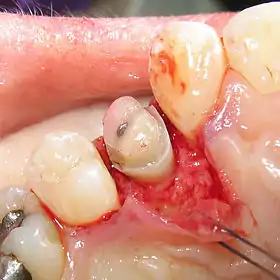

An alternative to surgical crown lengthening is orthodontic forced eruption, it is non-invasive, does not remove or damage the bone and can be cost effective. The tooth is extruded a couple of millimeters with simple bracketing of adjacent teeth and using light forces this will only take a couple of months. A fiberotomy is performed after crown lengthening and is easily performed by the general dentist. In many cases such as this one shown, surgery and extraction may be avoided if patient is treated orthodontically rather than periodontally.